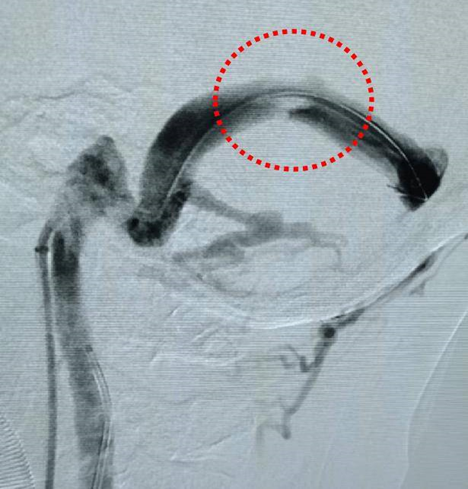

横窦:位于颅内,是硬脑膜窦的一部分,呈左右对称分布,因其走向呈横向而得名。它就像颅内的 “交通要道”,主要负责收集大脑部分区域的静脉血,将这些血液运输到其他部位。横窦的位置较为特殊,在颅骨内沿着特定的骨沟走行,其形态和结构有助于保证血液的顺畅流动。要是血管出现了问题——血管狭窄,就好比道路有了“歪路”“堵塞”,血液流动就不顺畅了(图4)。

图4 造影显示横窦狭窄严重

若横窦出现狭窄等病变,会影响静脉血回流,导致血液在局部瘀滞、涡流,进而引发一系列问题,如搏动性耳鸣。研究显示,横窦狭窄可能是静脉源性搏动性耳鸣的常见病因之一。